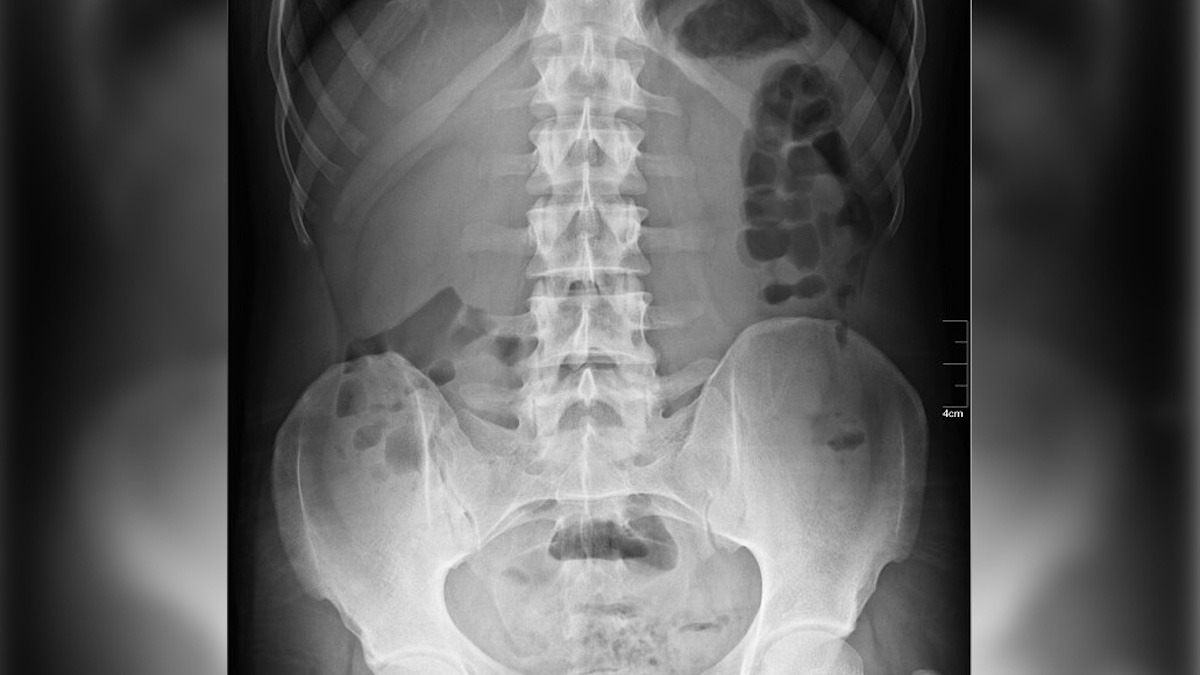

X ray through Wiki Commons Nevit Dilmen

Nonetheless, an X-ray revealed one thing astonishing that rapidly gained worldwide medical consideration: a calcified fetus, a uncommon situation often called a lithopedion or “stone child,” which had been in her physique for roughly 4 many years.

This calcified mass reportedly weighed about 4 kilos. The situation usually goes undetected for years and even many years, as many ladies expertise minimal to no signs. Prognosis sometimes happens solely when imaging is carried out for a distinct medical subject. On this Colombian case, docs theorized that the girl’s ache stemmed from the lithopedion urgent on her inner organs as she aged.